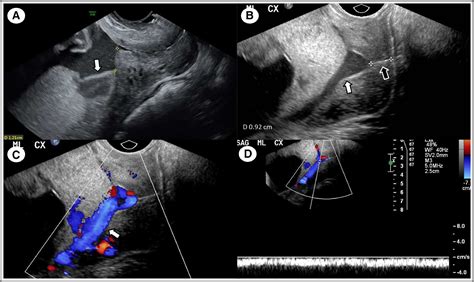

• placenta previa ultrasound images

Most women do not realize they have a Marginal Placenta Previa until it is detected during a routine anatomy ultrasound, usually around the 20th week of pregnancy. If you do experience symptoms, they are typically characterized by:

In a standard pregnancy, the placenta moves upward as the uterus grows and expands during the second and third trimesters. This is known as "placental migration." Because of this, many women diagnosed with a low-lying placenta or a marginal case in their second trimester find that the condition resolves itself before they reach full term. If the placenta is located within 2 centimeters of the cervix, doctors often categorize it as a low-lying placenta or marginal previa.